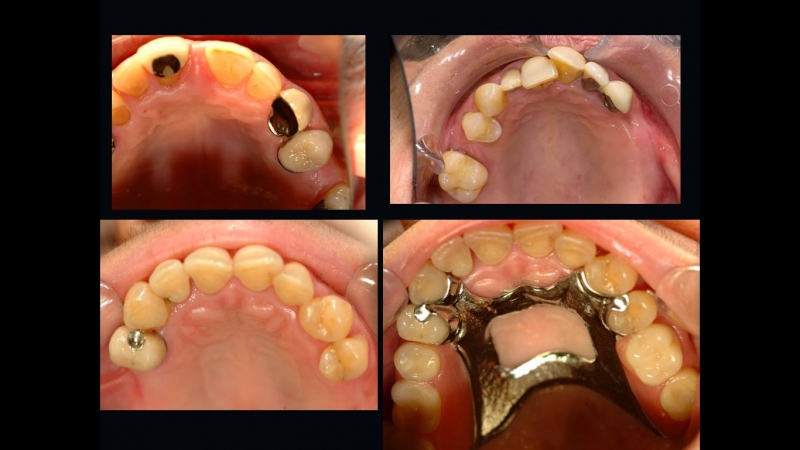

تتعدد أنواع الترميمات السنية التجميلية، ويعتمد اختيار النوع المناسب على حالة السن، درجة التلف، واحتياجات المريض الجمالية والوظيفية. ويهدف هذا التنوع إلى توفير حلول شاملة تناسب مختلف المشكلات السنية.

من أبرز الأنواع الحشوات التجميلية، والتي تُستخدم لعلاج التسوس أو الكسور البسيطة، وتتميّز بلونها القريب من لون الأسنان الطبيعي، مما يجعلها غير ملحوظة. وتُعد خيارًا مثاليًا للحفاظ على المظهر الجمالي للأسنان الأمامية والخلفية.

أما التيجان التجميلية، فهي تُستخدم في الحالات التي يكون فيها السن ضعيفًا أو مكسورًا بدرجة كبيرة، حيث تغطي السن بالكامل وتمنحه قوة إضافية وشكلًا طبيعيًا. وتُصنع التيجان من مواد عالية الجودة مثل الزيركون أو البورسلين، لضمان المتانة والمظهر الجمالي في آنٍ واحد.

القشور الخزفية أو الفينير تُعد من أكثر الحلول شيوعًا لتحسين شكل الابتسامة، حيث تُستخدم لتعديل لون الأسنان، إخفاء التشققات، أو تصحيح عدم انتظام بسيط في الشكل. وتتميز بنتائجها السريعة ومظهرها الطبيعي.

كما تشمل الترميمات السنية التجميلية الترميمات الجزئية أو الكاملة، والتي تُستخدم في حالات فقدان جزء من السن أو أكثر، ويتم تصميمها بدقة لتتناسب مع باقي الأسنان من حيث اللون والحجم.

في مركز سمايل لينك، يتم اختيار نوع الترميم بعناية بعد فحص شامل وتشخيص دقيق، مع مراعاة رغبة المريض والحالة الصحية للأسنان واللثة. هذا التنوع في الخيارات يضمن تقديم حل مثالي لكل حالة، مع تحقيق أعلى درجات الراحة والجمال للمريض.